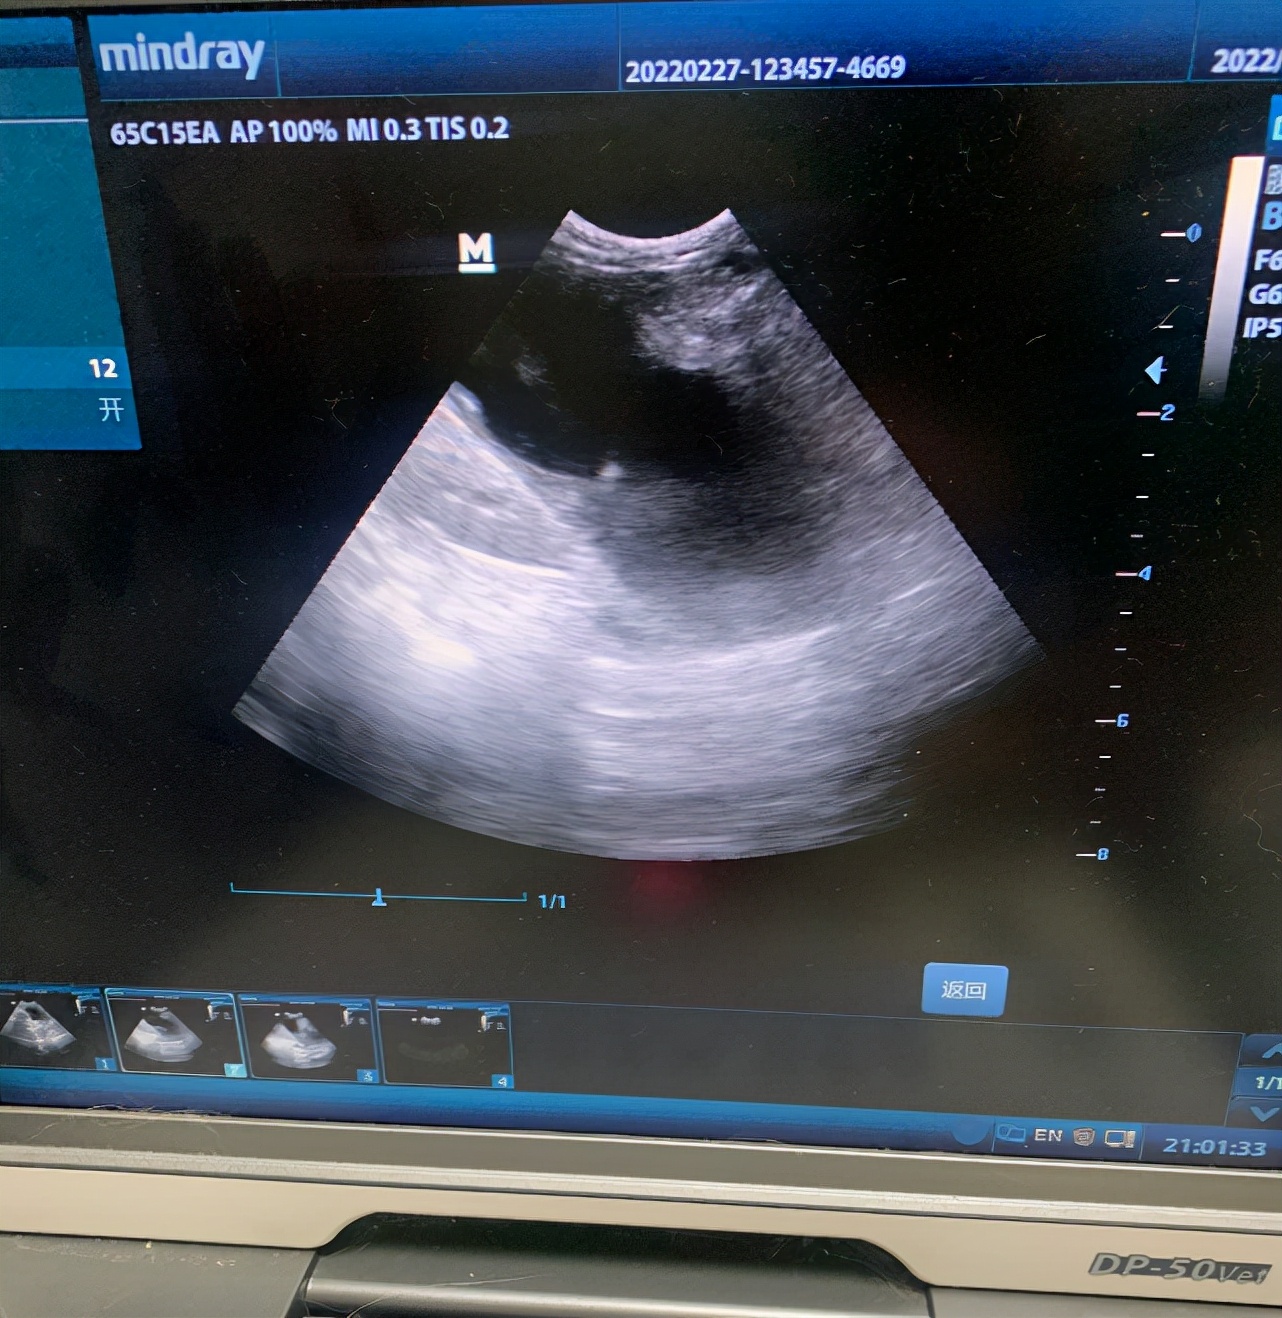

铲屎官答: 医生看治了半个月没有效果,又拉不出大便,就给它做了b超,b超发现有积液,没经过我同意,就抽了大概1毫升出来,是红色的血水混合物,中午抽的,晚上猫就死了,这个b超能看出积液吗?还是他戳伤了什么器官?

宠物医生回复: 这个b超看着确实是液性暗区,但是这个不知道当时医生做的角度是什么样的,所以不好判断。我的建议不是说医生怎么样,只代表我个人看法。

请您理解我觉得即使有少量积液也不用抽,重新复查生化。看结果如何。就算抽积液,量很少的情况下,并不容易抽出来。所以干脆就别动它。